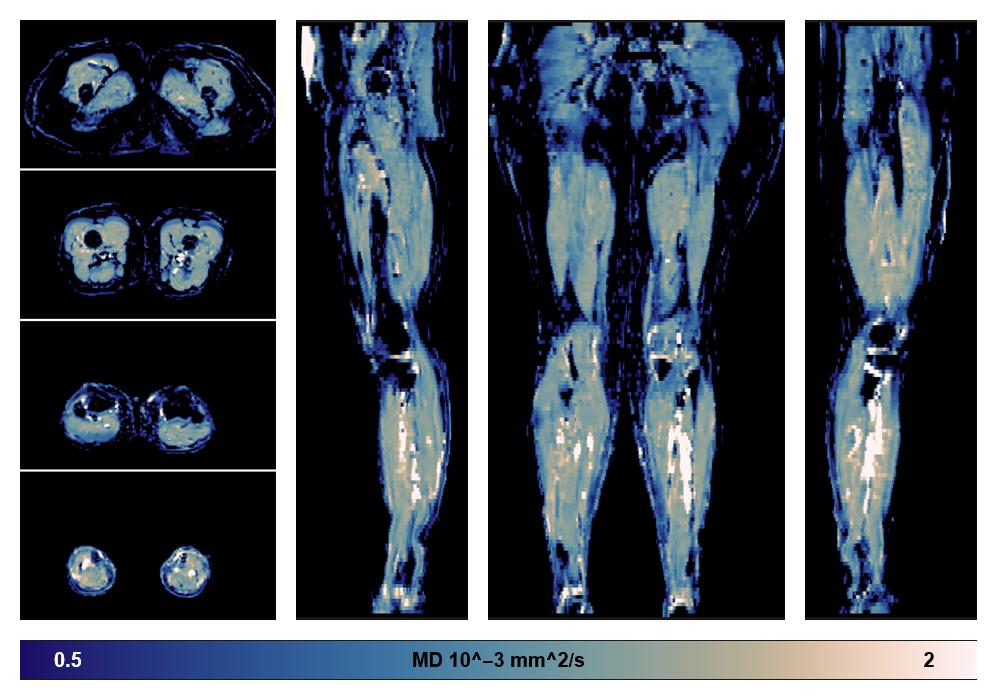

• Mean diffusivity

IVIM corrected whole leg muscle mean diffusivity obtained from diffusion tensor imaging.